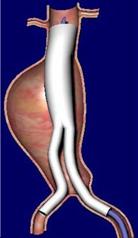

A less invasive option is to place a stent graft inside the vessel through catheters, known as endovascular aneurysm repair (EVAR). This method has a 10-year history. It is done without opening the abdomen, using small incisions in the groin under X-ray guidance.

In this method, the artificial graft is inflated at the aneurysm site and fixed internally with hooks. Patients are usually discharged in 1–2 days. However, this method is not suitable for all cases. The aneurysm may continue to enlarge or rupture even after the graft is placed, so periodic CT or Doppler ultrasound follow-up is necessary. Unlike open surgery, EVAR may not provide permanent cure.